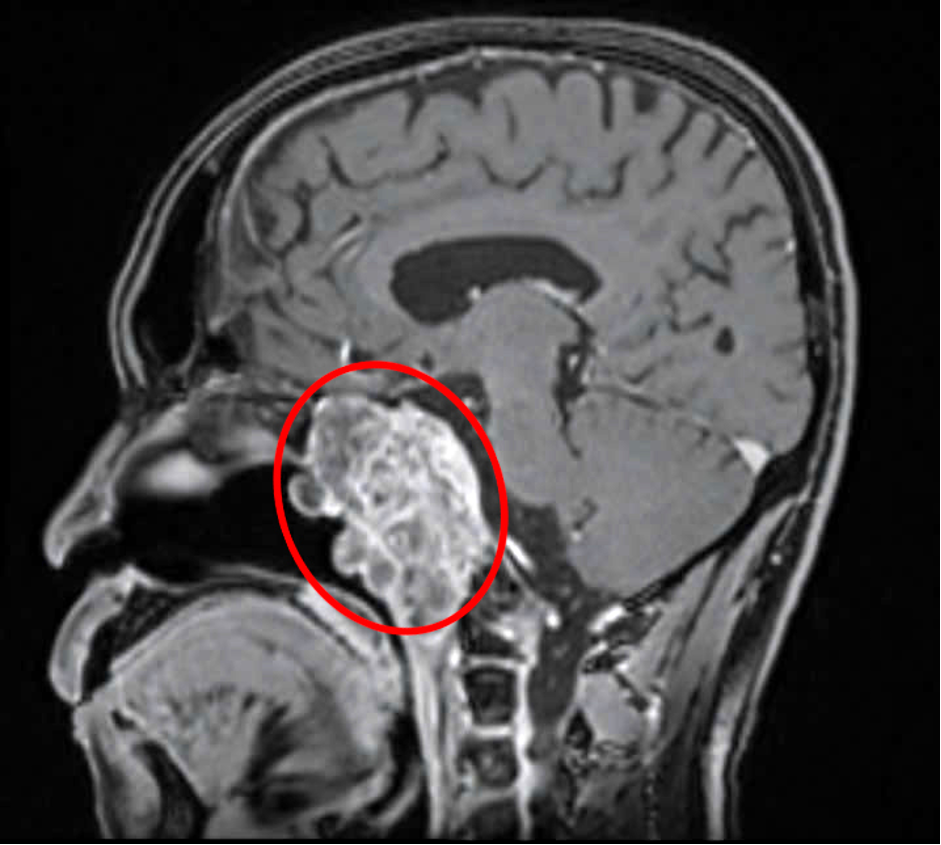

Hanh's tumor grew along the midline, extending backward and compressing the brainstem, causing headaches and dizziness. The tumor eroded bone and spread to both sides, invading part of the cavernous sinus and encasing major blood vessels. Hanh experienced double vision and limited eye movement due to the tumor's pressure on cranial nerves 3, 4, and 6.

The patient's chordoma had deeply invaded the base of the skull. Photo: Tam Anh General Hospital